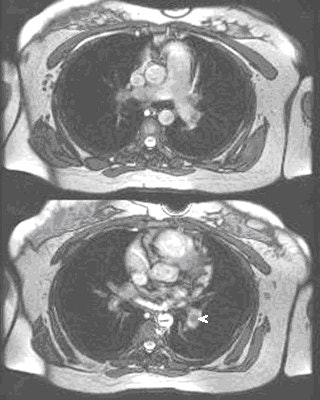

![]() |

| Noncontrast-enhanced MR of pulmonary embolism. A 36-year-old woman, 12 weeks pregnant, presented with shortness of breath. Coronal (above) and axial (below) and axial FIESTA views demonstrate left main pulmonary artery embolus (arrowheads). Images courtesy of Dr. Patrick Colletti. |